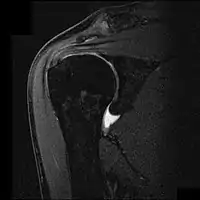

![]() Imagen por resonancia magnética nuclear mostrando el pinzamiento y ruptura parcial del tendón del músculo supraespinoso. | ||

En el caso de complementar con pruebas imagen, a menudo se utiliza la radiografía, el examen por ultrasonido y la resonancia magnética nuclear para confirmar la sospecha diagnóstica. La radiografía permite descartar que existan espolones o anomalías en la morfología del acromion que se hayan constituido como causa del síndrome, así como otras patologías identificables a través de esta prueba de imagen como la tendinitis calcificante, fracturas o neoplasias. El ultrasonido es una forma rápida, precisa y barata de evaluar posibles roturas parciales del manguito.[13]Sin embargo, dentro de las pruebas radiológicas, la resonancia magnética nuclear se considera el gold standard para evaluar roturas parciales o totales de los tendones afectados, aunque un estudio halló que esta solo se realiza en el 5,2% de los sujetos afectados.[14]